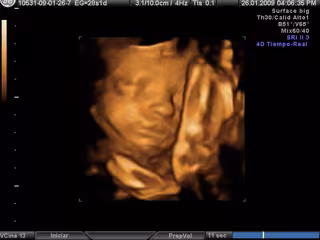

Ecografía en 3D- embarazo

El juez estima de este modo la demanda que presentaron los progenitores por falta de oportunidad para abortar, ya que en la ecografía de la semana 20 no se comprobaron los órganos sexuales del feto y se confió en la amniocentesis que le había sido practicada a la mujer, que determinó que el feto era un varón.

Semanas después, en otra ecografía se advirtió que los genitales tenían apariencia femenina, por lo que existía una discordancia sexual.